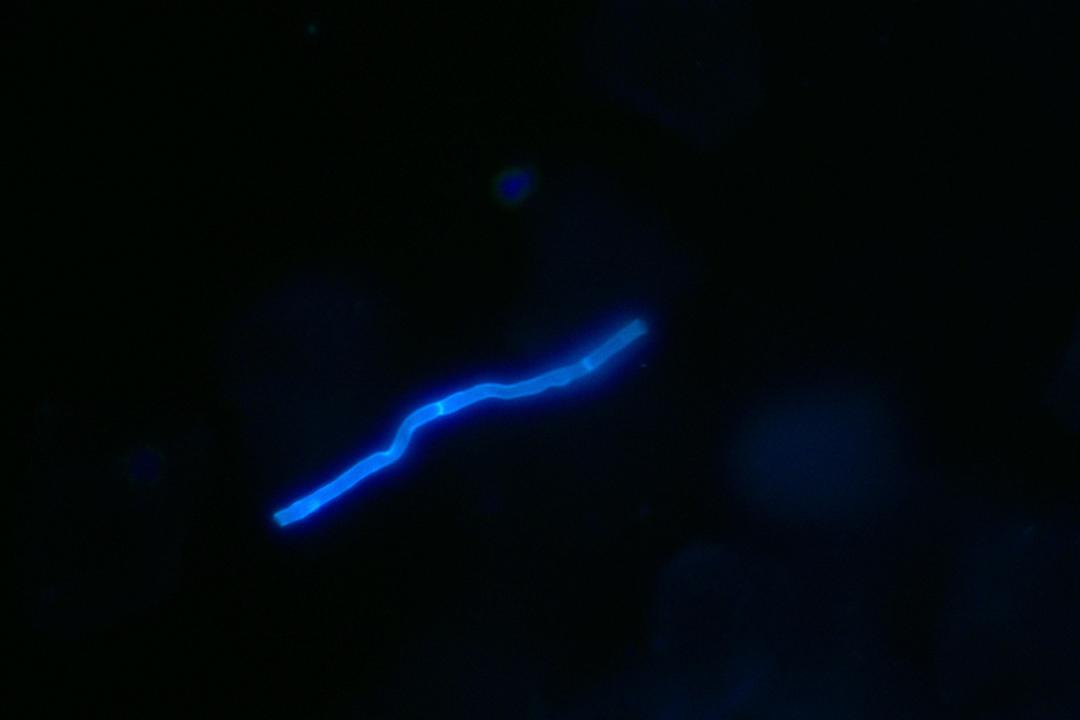

素履之往

荧光镜检下的真菌菌丝,像一条孤单蠕动的草履虫,菌心所向 素履之往,不知它将去向何方,但它着实带来瘙痒。